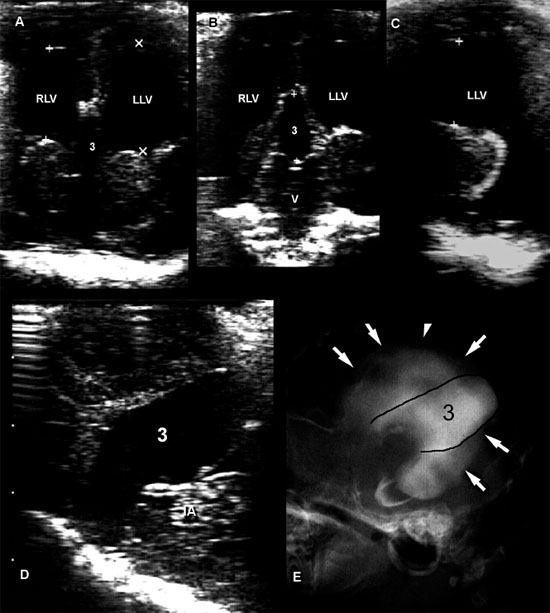

Several methods have been proposed for evaluating enlarged lateral ventricles on sonograms (Figure 1.10 and Table 1.1). The degree of ventriculomegaly ranges from the ventricles being only slightly enlarged to ventricles occupying most of the brain. Midline structures between the lateral ventricles are intact in some animals, but the lateral ventricles become confluent in others (Figure 1.11).

Figure 1.10. Measurement of the lateral ventricles in a 3-month-old Chihuahua. A: Transverse sonogram at the level of the interthalamic adhesion showing measurement using the method of Hudson et al. (1990) The lateral ventricular height can be compared with the cerebral mantle thickness (the thickness of the parenchyma dorsal to the lateral ventricle) to obtain the ventricle-mantle ratio. B: Transverse sonogram at the level of the pituitary gland showing measurement by using the method of Spaulding and Sharp (1990). Another method of measurement calculates the dorsoventral measurement of the lateral ventricle as a percentage of the dorsoventral measurement of the brain. RLV, right lateral ventricle.

Figure 1.11. Variability in expansion of the ventricular system in hydrocephalus. Additional images from the brain of the 3-month-old Chihuahua shown in Figure 1.10 indicate that the temporal horns are minimally affected, but there is a confluence of the rostral horns. The third ventricle is not enlarged. Sonograms of another Chihuahua in Figure 1.9 show that ventriculomegaly involves the temporal horns, as well as rostral horns and central parts, and there is enlargement of the third ventricle in that dog. Midline structures remain mainly intact, however. A: Rostral transverse sonogram. B: Parasagittal sonogram. H, hippocampus; LLV, left lateral ventricle; RLV, right lateral ventricle; SS, splenial sulcus; and T, thalamus.

It may also be useful to evaluate the amount of brain tissue spared by the dilated ventricles. Animals with very little brain tissue commonly have severe neurological deficits, although that is not always true (Figure 1.12).

The suggested methods of measurement are not always useful (Table 1.1). Some animals may have minimal enlargement in the described planes for measurement but have greatly enlarged ventricles in other areas, such as the caudal part of the central horn and the temporal horn. The third or fourth ventricles may also be enlarged. Sonographers should be careful to record these findings, as well as any other abnormalities, including additional anomalies or masses that may be related to the ventriculomegaly.

Agenesis of the corpus callosum has been reported uncommonly in dogs (Spaulding and Sharp 1990). In people, sonographic findings include lateral separation of the rostral horns and bodies of the lateral ventricles, elevation and variable dilation of the third ventricle, and dilation of the occipital horns. The bundles of Probst cause concavity of the medial wall of the lateral ventricles. In dogs, enlargement and dorsal displacement of the third ventricle can be seen (Figure 1.19).

Figure 1.19. Agenesis of the corpus callosum and hydrocephalus. Images of the brain of a young puppy with severe neurological deficits. The right and left lateral ventricles are greatly dilated. The third ventricle is enlarged and displaced dorsally. A: Rostral transverse sonogram showing marked dilation of the lateral ventricle. B: Transverse sonogram angled caudally to image the vermis of the cerebellum. The third ventricle is enlarged and displaced dorsally. C: Parasagittal sonogram with the ultrasound beam angled laterally to image the enlarged left lateral ventricle. D: Sagittal sonogram showing marked enlargement and dorsal displacement of the third ventricle. E: Radiograph of the brain after ventriculography was performed using an iodinated contrast medium. The lateral ventricles (arrows) are greatly dilated. The third ventricle (outlined in black) is greatly dilated and displaced dorsally. 3, third ventricle; IA, interthalamic adhesion; LLV, left lateral ventricle; RLV, right lateral ventricle; and V, vermis.